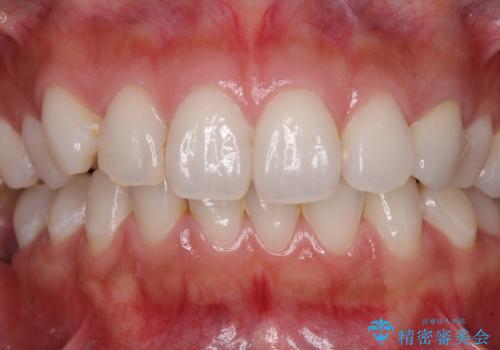

- 前歯の保険のかぶせものをセラミックに替えたいと来院された患者様です。

保険のかぶせもの特有の変色や縁の金属色、歯根が一部見えている点が気になるとのことでした。

土台の金属を除去してファイバーコアによる土台植立を行い、オールセラミッククラウンにて補綴することとしました。

前歯1本の治療では、オールセラミッククラウンといえども周囲と調和しなければ自然な仕上がりにはなりません。

今回は既製の色調のセラミックを選択されましたが、もっと色合いにこだわりたい場合には、オーダーメイドタイプのセラミッククラウンをご選択いただいています。